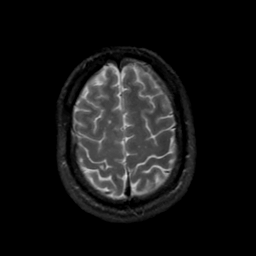

MR Study #17, July 7, 1991 -- Slice #41

[Home][Help][Clinical][Tour 1][Tour 2] Slice 41